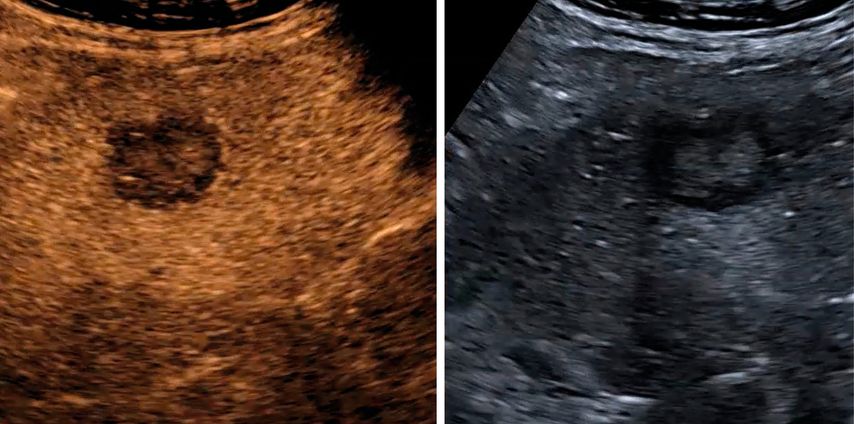

In der früharteriellen Phase zeigen benigne Läsionen wie Hämangiome typische Füllungsmuster ohne «wash-out» in der Portal- oder Spätphase (Abb.1). Maligne Läsionen hingegen weisen meist ein rasches «wash-out» auf und stellen sich in der Spätphase hypokontrastiert dar (Abb.2).3,4

Abb. 1: Typisches Kontrastmittelverhalten eines Hämangioms in der Spätphase mit Hyperenhancement gegenüber dem umgebenden Leberparenchym (rechts)

Abb. 2: Darstellung einer hochgradig Metastasen-suspekten Raumforderung bei Mamma-Neoplasie im linken Leberlappen im B-Bild-Modus (rechts) sowie in der Spätphase nach Gabe von 1,6 ml SonoVue® mit Darstellung eines deutlichen «Wash-out»-Phänomens in der Spätphase 4 Minuten nach Injektion des Kontrastmittels (links)